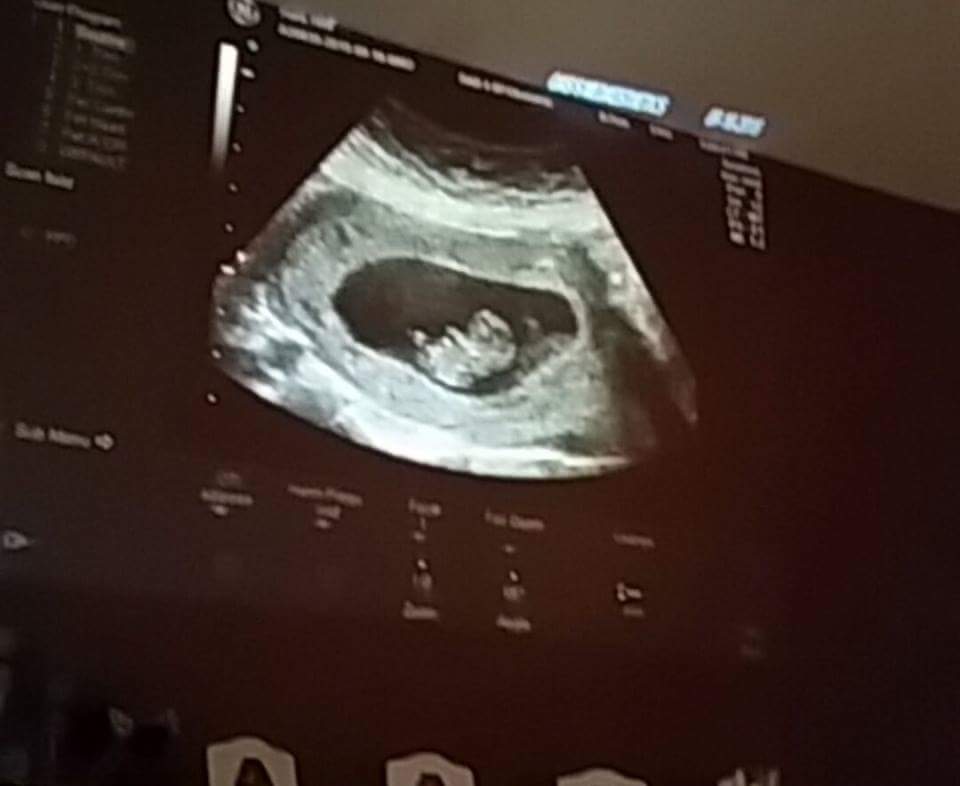

Well... I am about 8w4d and saw my little gummy bear and heartbeat today. We had a loss in April at 11w and I jUst can't get that thrill and excitement yet...